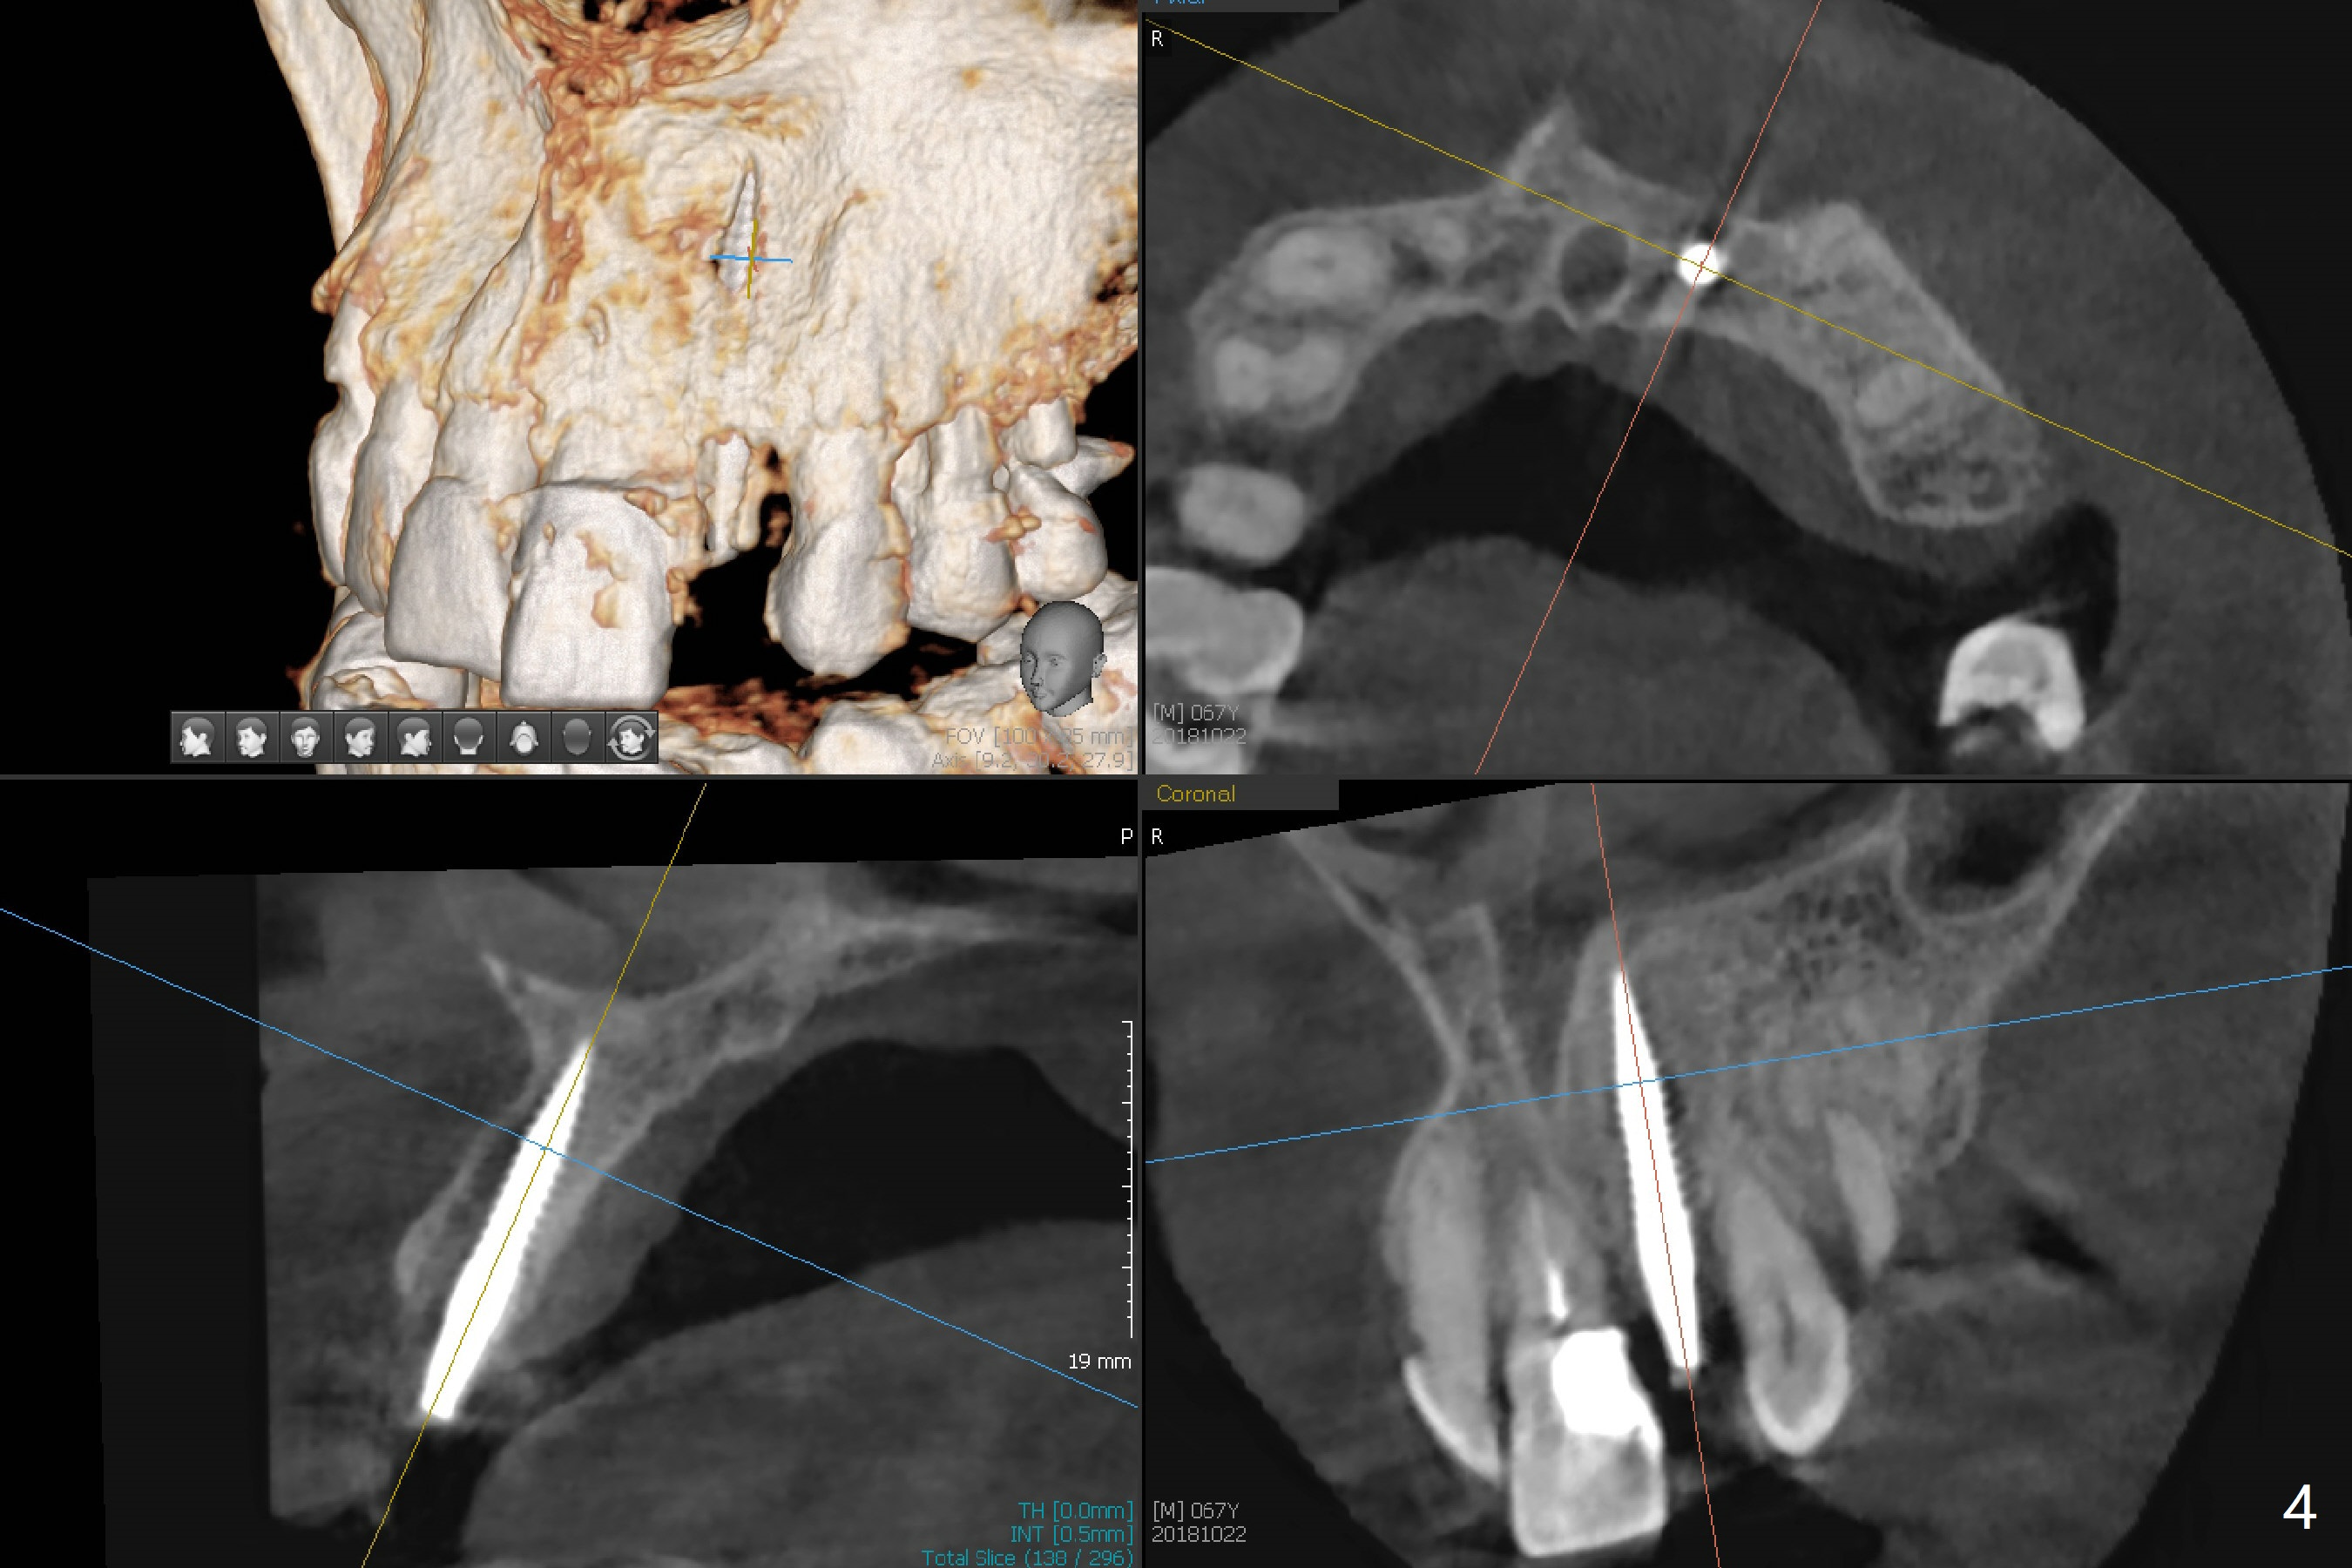

When the 67-year-old man returns for #23-26 crown/FPD cementation, the tooth #10 has fractured with necrotic pulp (Fig.1) and periapical radiolucency (Fig.2 (CT coronal section) *). He requests immediate implant since he has difficulty in getting ride from out of state. After curettage of the apical granulation tissue, a 3x16(2) mm 1-piece implant is placed with 20 Ncm because of slight overprep using 2 mm drill (Fig.3). Postop CT shows that the implant does not seem to be small (Fig.4). The fracture of the tooth #10 is related to edge-to-edge occlusion with the tooth #22 while the lower restoration is being fabricated in lab (Fig.5). It is easy to achieve occlusal clearance when the immediate provisional is fabricated with normal overjet. The density of the bone immediately next to the implant increases 6 months postop (Fig.6 *). The soft tissue also looks normal.